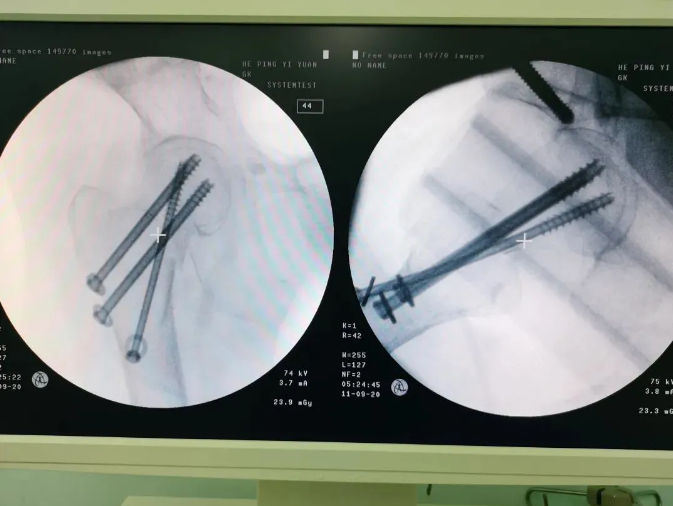

規(guī)劃入路

天璣機器人置入螺釘

螺釘置入后

天璣?骨科手術機器人的加入,能夠協(xié)助醫(yī)生為需要進行手術的患者提供更安全、優(yōu)質(zhì)、高效的醫(yī)療服務,幫助患者清除病灶,守護患者健康,提高患者生活質(zhì)量。在天璣?骨科手術機器人的協(xié)助下,術中患者切口僅三個小孔,出血量少;術后陳婆婆經(jīng)一段時間的康復訓練便可下床活動,目前已康復出院。